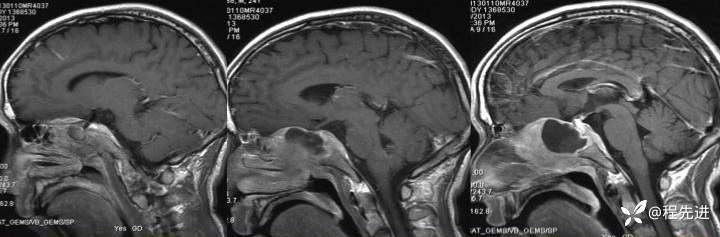

【患者信息】:男,24岁

【现病史及既往史】:患者1月前无明显诱因出现右脸麻木,之后出现复视,20天前发出现右眼失明伴头痛

T1:

增强: